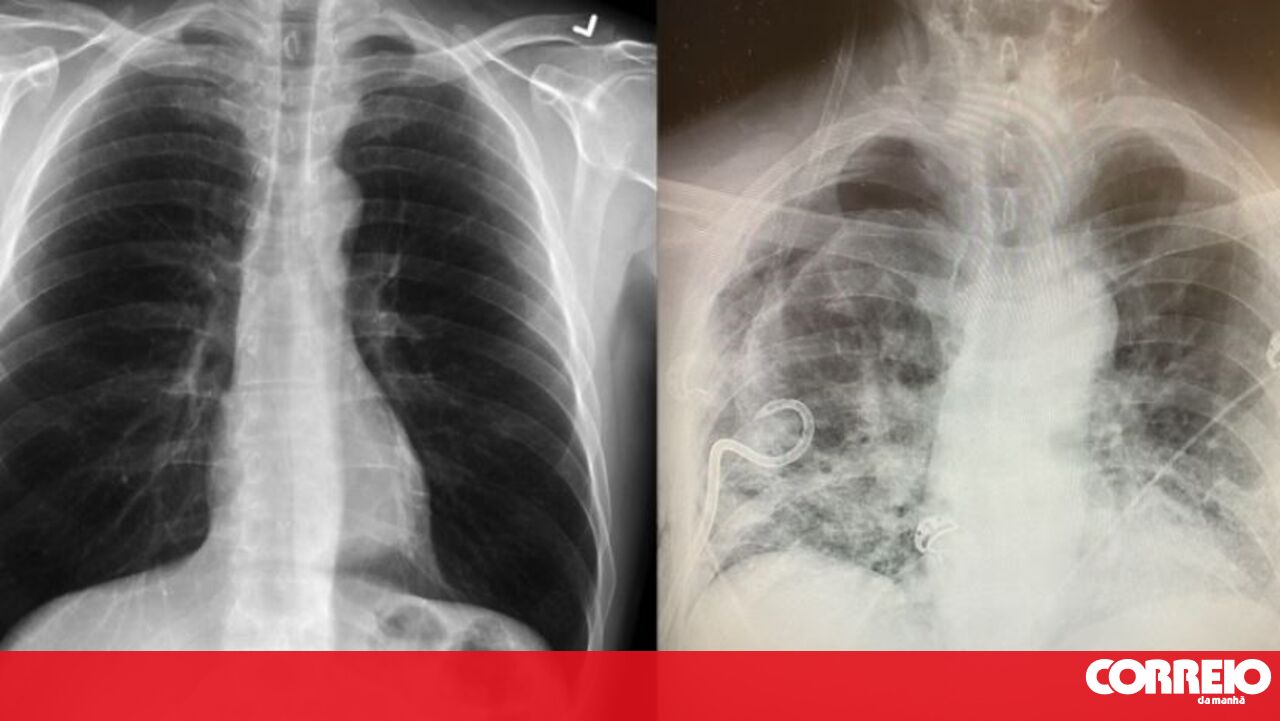

Uma doente, cujos pulmões foram gravemente danificados pela Covid-19, recebeu um transplante de pulmão de doadores vivos.Um estudo revelado no início deste ano mostrou que mais de 1700 pacientes da cidade chinesa de Wuhan, considerada o epicentro da pandemia, apresentaram raio-X onde era possível observar danos graves nos pulmões meses após a infeção.

Um estudo revelado no início deste ano mostrou que mais de 1700 pacientes da cidade chinesa de Wuhan, considerada o epicentro da pandemia, apresentaram raio-X onde era possível observar danos graves nos pulmões meses após a infeção.